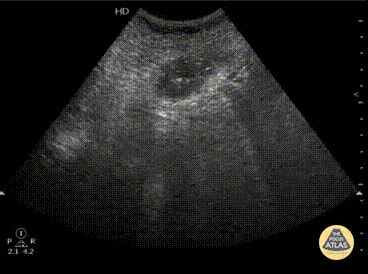

An elderly male presented with unyielding bilious vomiting and abdominal pain. A RUQ extended view shows gallstone ileus with the hypoechoic stone creating an acoustic shadowing artifact. Here, the gallstone is lodged in the small bowel and can arise from frequent cholecystitis creating a fistula between the gallbladder and small bowel. Image courtesy of Robert Jones DO, FACEP @RJonesSonoEM Director, Emergency Ultrasound; MetroHealth Medical Center; Professor, Case Western Reserve Medical School, Cleveland, OH View his original post here